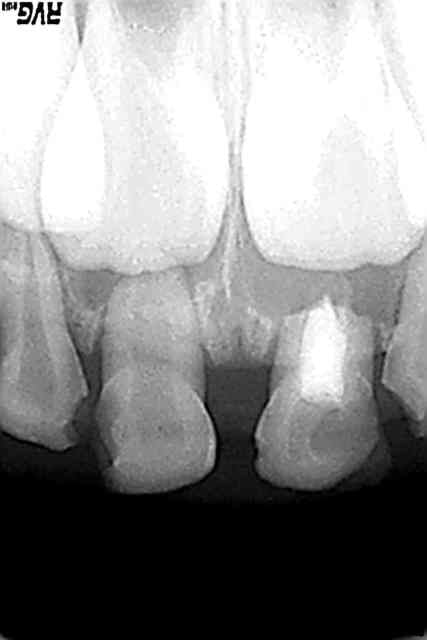

sharon: pulpec a 3 ans sur dt necrosee et rx a 5 ans

61 suite zhfmok - Eugenol

Ttt 61 um5l69 - Eugenol